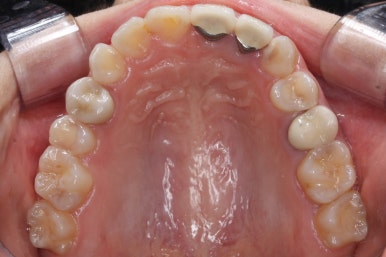

초진 때의 입안 모습입니다.

앞니는 고른 편이였으나 군데군데 틈새가 있었습니다. 약간 삐뚠 모습도 보이지만 환자분께서 개선을 하고자 했던 부분은 아래쪽 어금니 1개가 없는 자리였습니다.

장치를 붙인 모습입니다.

개선을 하고자 하는 어금니에만 장치를 붙였고 다른 치아는 움직이지 않아야 하기 때문에 강한 지지대가 되어야 할 부분에 미니스크류를 식립했습니다.

치료 과정을 순차적으로 보겠습니다.

임플란트를 식립하기 위한 공간이 서서히 확보가 되어 가는 것이 보입니다. 어금니만한 사이즈로 공간이 확보가 되면 식립이 이뤄지죠.

불과 4개월만에 장리가 충분히 확보된 모습입니다.